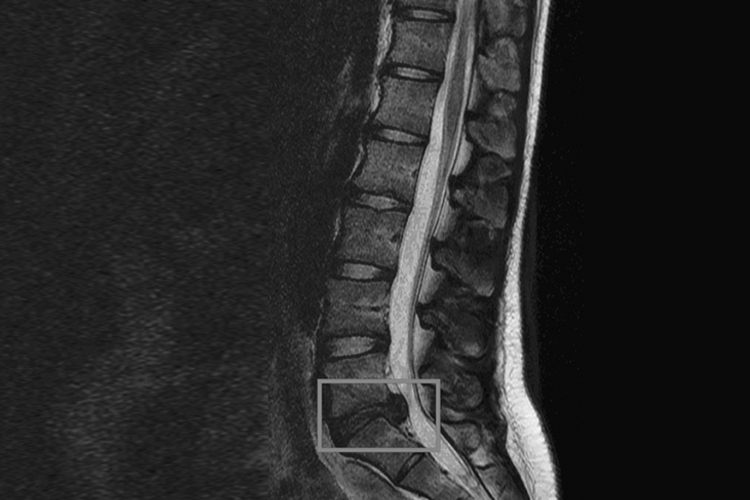

腰椎间盘突出症的主要表现为腰腿疼痛、活动受限等,通常是由于腰椎间盘退行性改变,髓核突出,刺激和压迫神经引起的。

腰椎间盘突出症大部分出现在腰5/骶1(L5-S1)两个节段,其次也可见于腰4/5(L4-L5)。腰痛和一侧下肢放射痛是腰椎间盘突出症的主要症状。腰痛常发生于腿痛之前,也可两者同时发生,疼痛可沿坐骨神经传导,直达小腿外侧、足背或足趾,或向大腿前方产生放射痛。

腰椎间盘突出症是腰椎间盘退行性改变或损伤后,在外力的作用下纤维环部分或全部破裂,髓核突出,刺激或压迫窦椎神经、神经根、马尾神经,引起腰腿疼痛。导致腰椎间盘退变和损伤的常见因素包括先天结构异常、遗传、慢性劳损等。